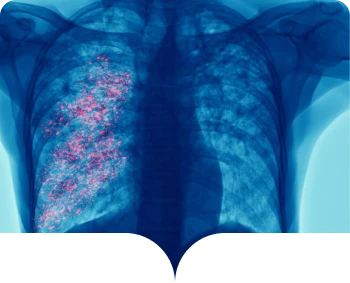

Virus Sincicial Respiratorio o VSR

es un virus frecuente que infecta la nariz, la garganta, los pulmones y que generalmente causa síntomas leves

y similares a los de un resfriado.1,2

Algunas personas, especialmente los adultos mayores y los bebés menores de 6 meses, pueden necesitar hospitalización. El VSR puede causar bronquitis (inflamación de las vías respiratorias pequeñas en el pulmón) y neumonía (infección en los pulmones).1,2